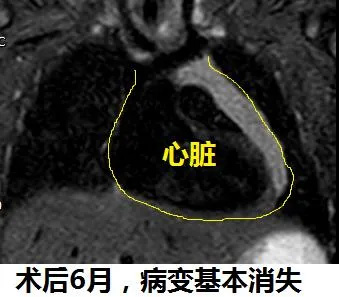

患儿14天时,石文媛主任为其进行了超声引导经皮淋巴管畸形注药治疗。术中,石文媛主任将一根纤细的治疗针精准置入瘤体内,随着病变体积的缩小,被压肺脏逐渐恢复了张力。治疗过程如同行云流水一气呵成,术中没有发生大出血、没有出现心肺功能障碍,手术顺利完成!由于采用了微创治疗技术,患儿平稳度过了术后危险期并迅速恢复,1周后小患者康复出院。超声引导注药治疗后3个月,经超声、核磁检查均发现,病变已基本消失。目前,16个月的小患儿发育良好,活泼好动,病变已完全消失。